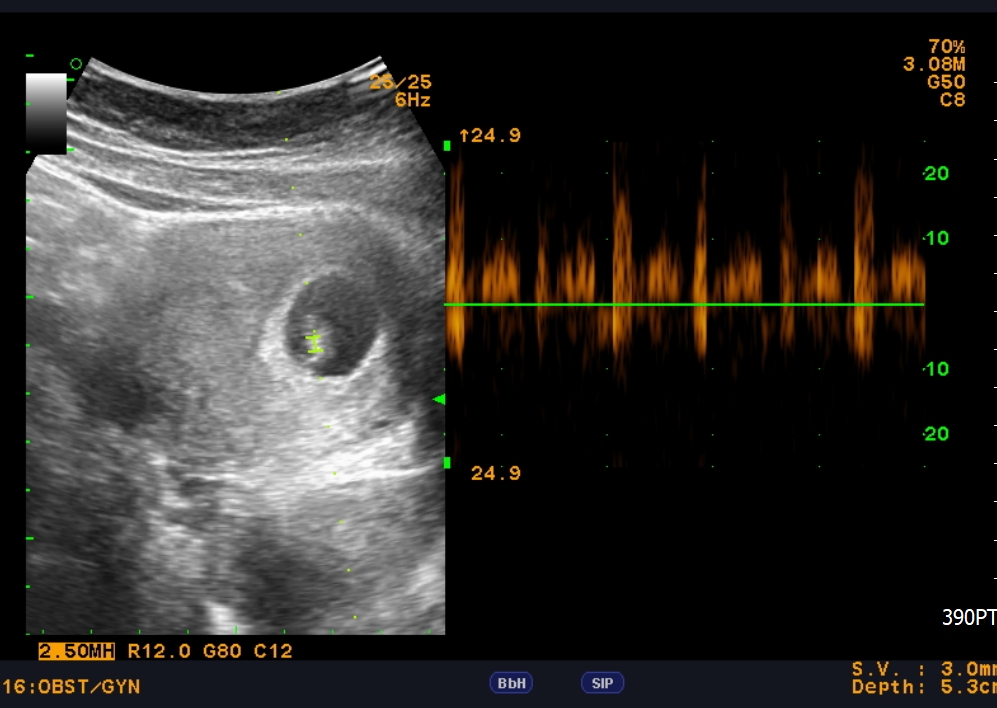

ORA受孕窗期檢測

宮喜方案為預先抽血的方式 可將血液先行保存,若有需求,可以立即啟動分析檢測 這樣就可以 #省去花費一個療程的時間和費用。可惜,希望再次化為泡影。 第三次植入前,李醫師建議可進行ORA 受孕窗期檢測藉由分析檢測找出是否有受孕窗期偏移的情況,而導致無法成功懷孕。與他人不同,需要提前的植入時間

檢測結果顯示,Yvonne的最佳植入時機需要提前,這個發現為第三次治療帶來一線曙光。Yvonne :「第三次的試管療程時,我已經做好最壞的打算了」。Yvonne心想,或許真的是與孩子無緣... 然而,奇蹟總是在付出一切努力之後降臨。 在中山醫醫療團隊的專業協助下,這對夫妻終於迎來了期待已久的好消息。 如今,他們的小龍子已經平安降生。 Yvonne回憶起當時,每次下班後趕著到醫院,再匆匆趕回家,其實真的很累。 「但現在看著寶寶,就覺得再辛苦都值得。」